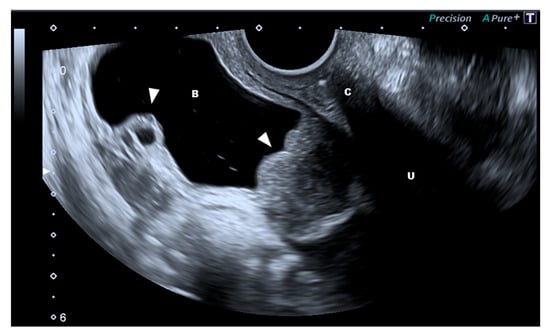

3.4. The Bladder and Ureter